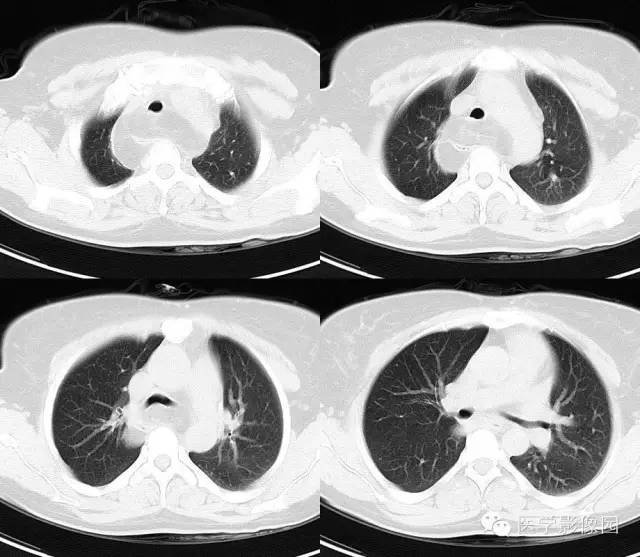

病史:患者,女,41 岁。因“活动后心悸、气促半年,加重伴咳嗽 2 月余”入院。

肺窗

影像学表现:后上纵隔见一不规则形低密度影,CT 值大部分为负值,其内可见有条状分隔,病灶边界较清,向上延伸至锁骨以上层面,增强扫描未见明显强化,气管受压前移。纵隔内未见明确淋巴结肿大,胸腔未见明确积液征。

诊断:(后上纵隔)脂肪瘤

讨论:脂肪瘤含大量脂肪组织,一般密度比较均匀,边界一般清楚,其内可见纤维间隔,增强扫描病灶主体无强化,纤维间隔可见强化。